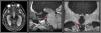

The irrigation of the thalamus depends mainly on the thalamoperforating arteries. There are many anatomical variations in these arteries, the best known being the artery of Percheron. We report a case of a 13-year-old male presented with headache and decline in his mental status. Imaging features showed obstructive hydrocephalus secondary to a mass at the level of the mesencephalon so an endoscopic third ventriculostomy was performed. During the procedure a thalamoperforating artery was encountered at the level of the tuber cinereum limiting the perforation of the third ventricle floor. The present case emphasizes the importance of knowing the anatomy of these arteries and the identification of their main variants during neurosurgical procedures.